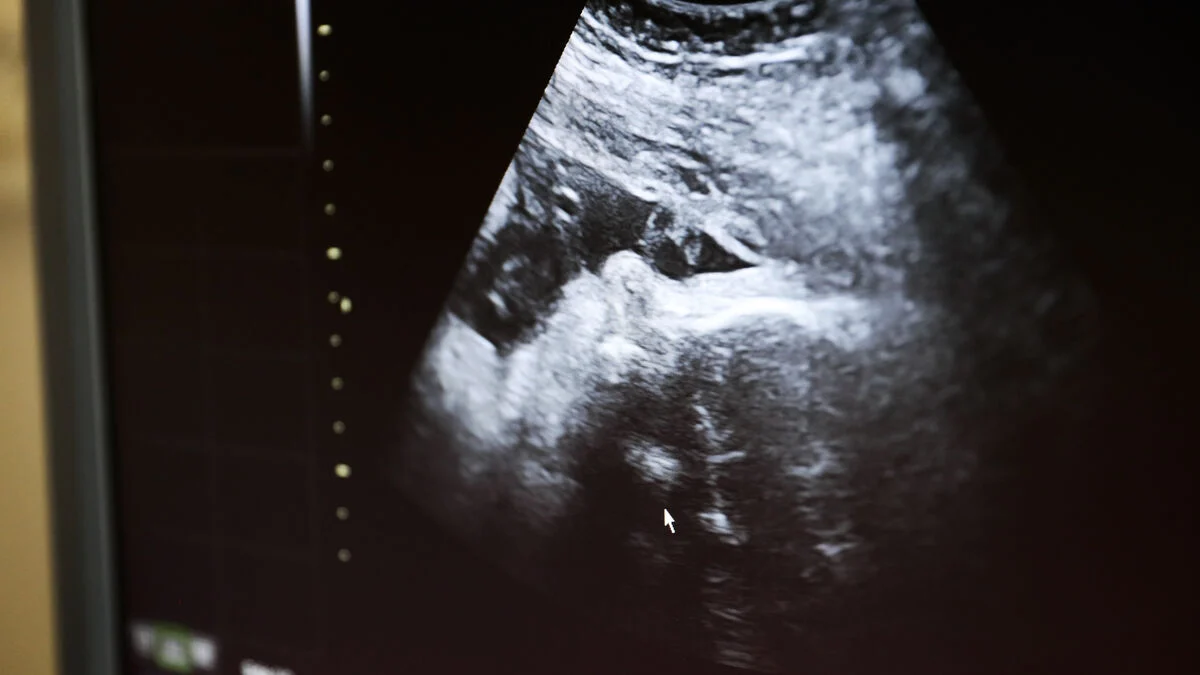

I dagsläget används KUB-testet (Kombinerat Ultraljud och Biokemi) som standardmetod för att bedöma risken för kromosomavvikelser, främst Downs syndrom, hos fostret under tidig graviditet. När KUB-testet indikerar förhöjd risk, erbjuds ofta NIPT (Non-Invasive Prenatal Test) som ett kompletterande test för att ge mer precisa resultat innan mer invasiva metoder övervägs.

Samtidigt kan KUB-undersökningen upptäcka vissa anatomiska avvikelser och andra tillstånd som NIPT inte kan identifiera. Vid ett KUB-test genomförs ett ultraljud där nackuppklarning mäts, och detta ger möjlighet att observera även andra aspekter av fostrets utveckling.